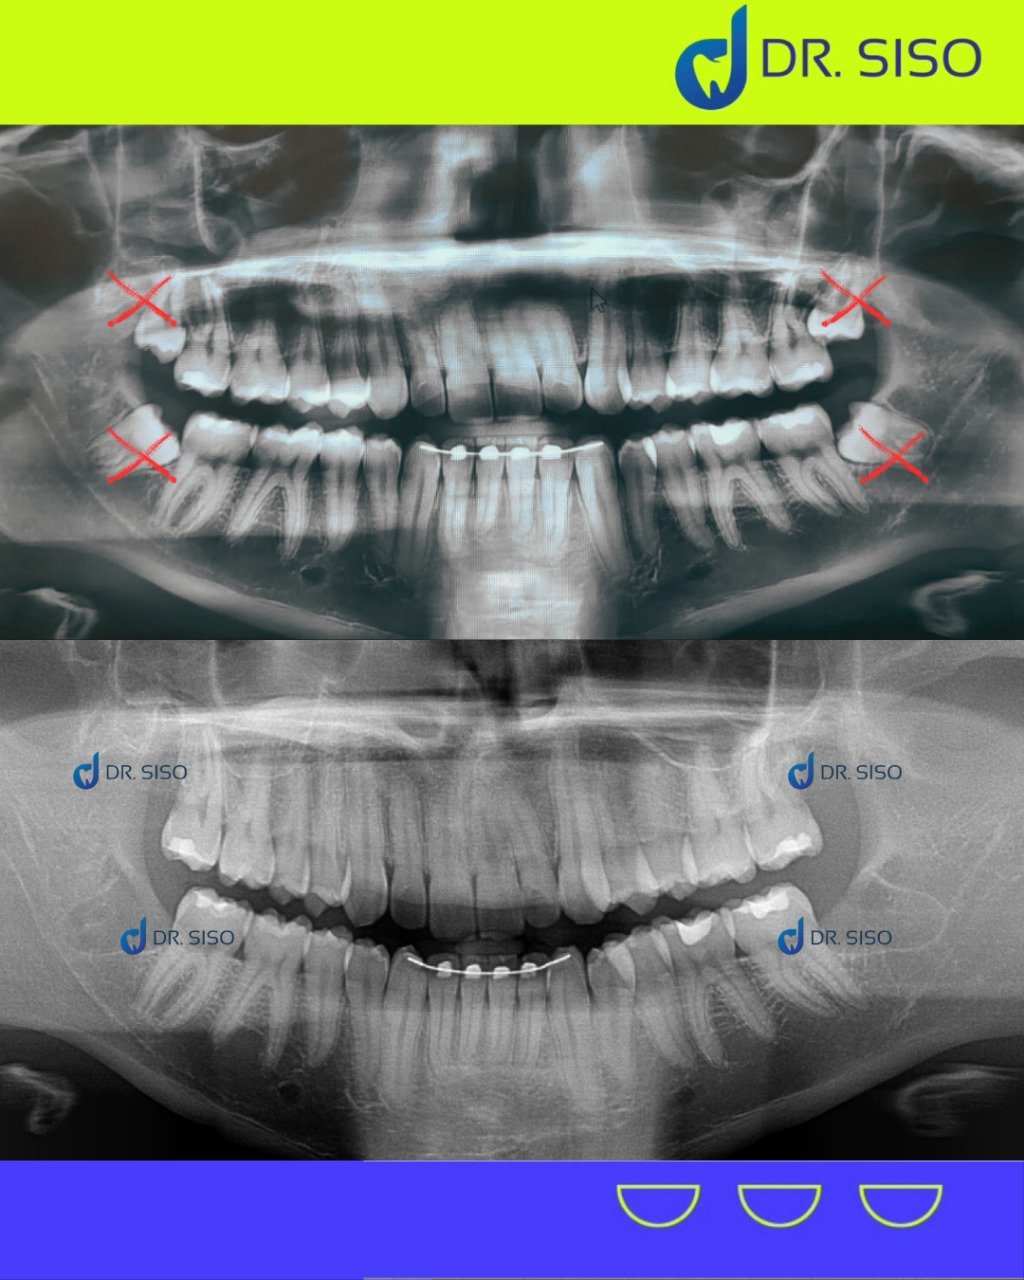

Aquele incômodo no fundo da boca pode ser causado pelos sisos! Quando não há espaço suficiente para nascerem corretamente, eles podem provocar dor, inchaço e até infecções. A extração do siso é um procedimento seguro que evita problemas futuros e alivia o desconforto.

Sim, em muitos casos. Mesmo sem dor, o siso pode estar mal posicionado, pressionando outros dentes, causando reabsorção óssea ou prejudicando a mordida. A avaliação clínica e radiográfica é essencial para decidir com segurança.